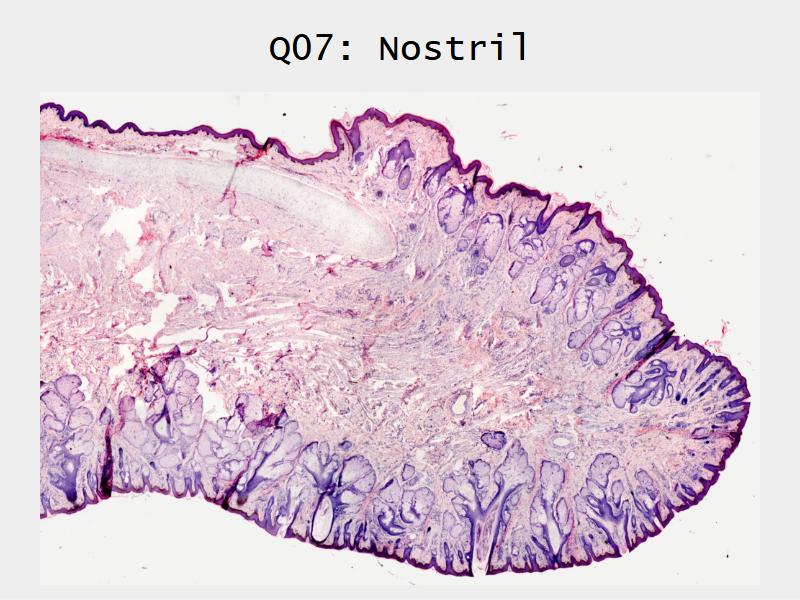

Slides: Respiratory System

- Slide 71: Nostril

Nostril

Function of the nasal cavity?

Function of the nasal cavity?

- Warm

- Moisture

- Filter

- Smell